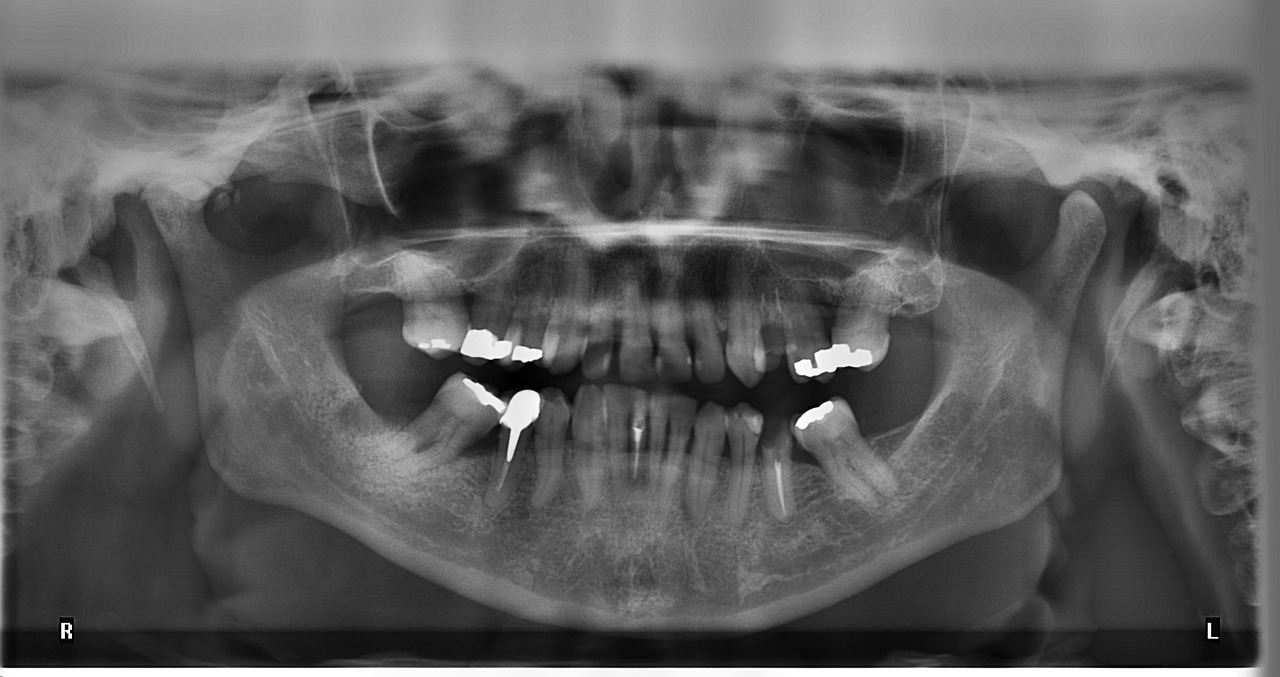

Jak działa RTG zęba i czy jest bezpieczne?

RTG zęba odgrywa kluczową rolę w diagnostyce stomatologicznej, umożliwiając lekarzom...

Kiedy i dlaczego stomatolog może zlecić wykonanie RTG zęba?

Stomatolog może zlecić wykonanie RTG zęba w różnych sytuacjach, w...